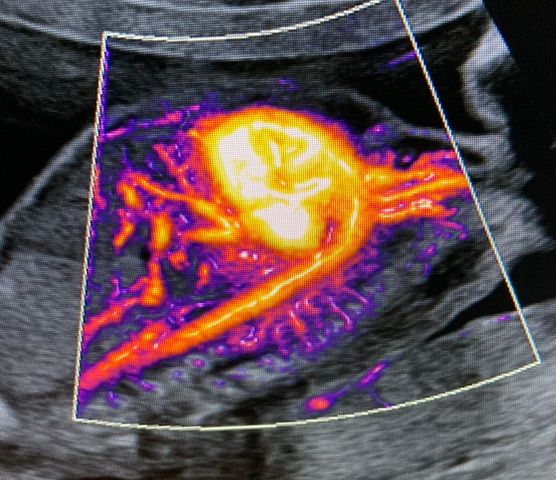

• Flussimetria Doppler

• Ecocardiografia fetale

185 €